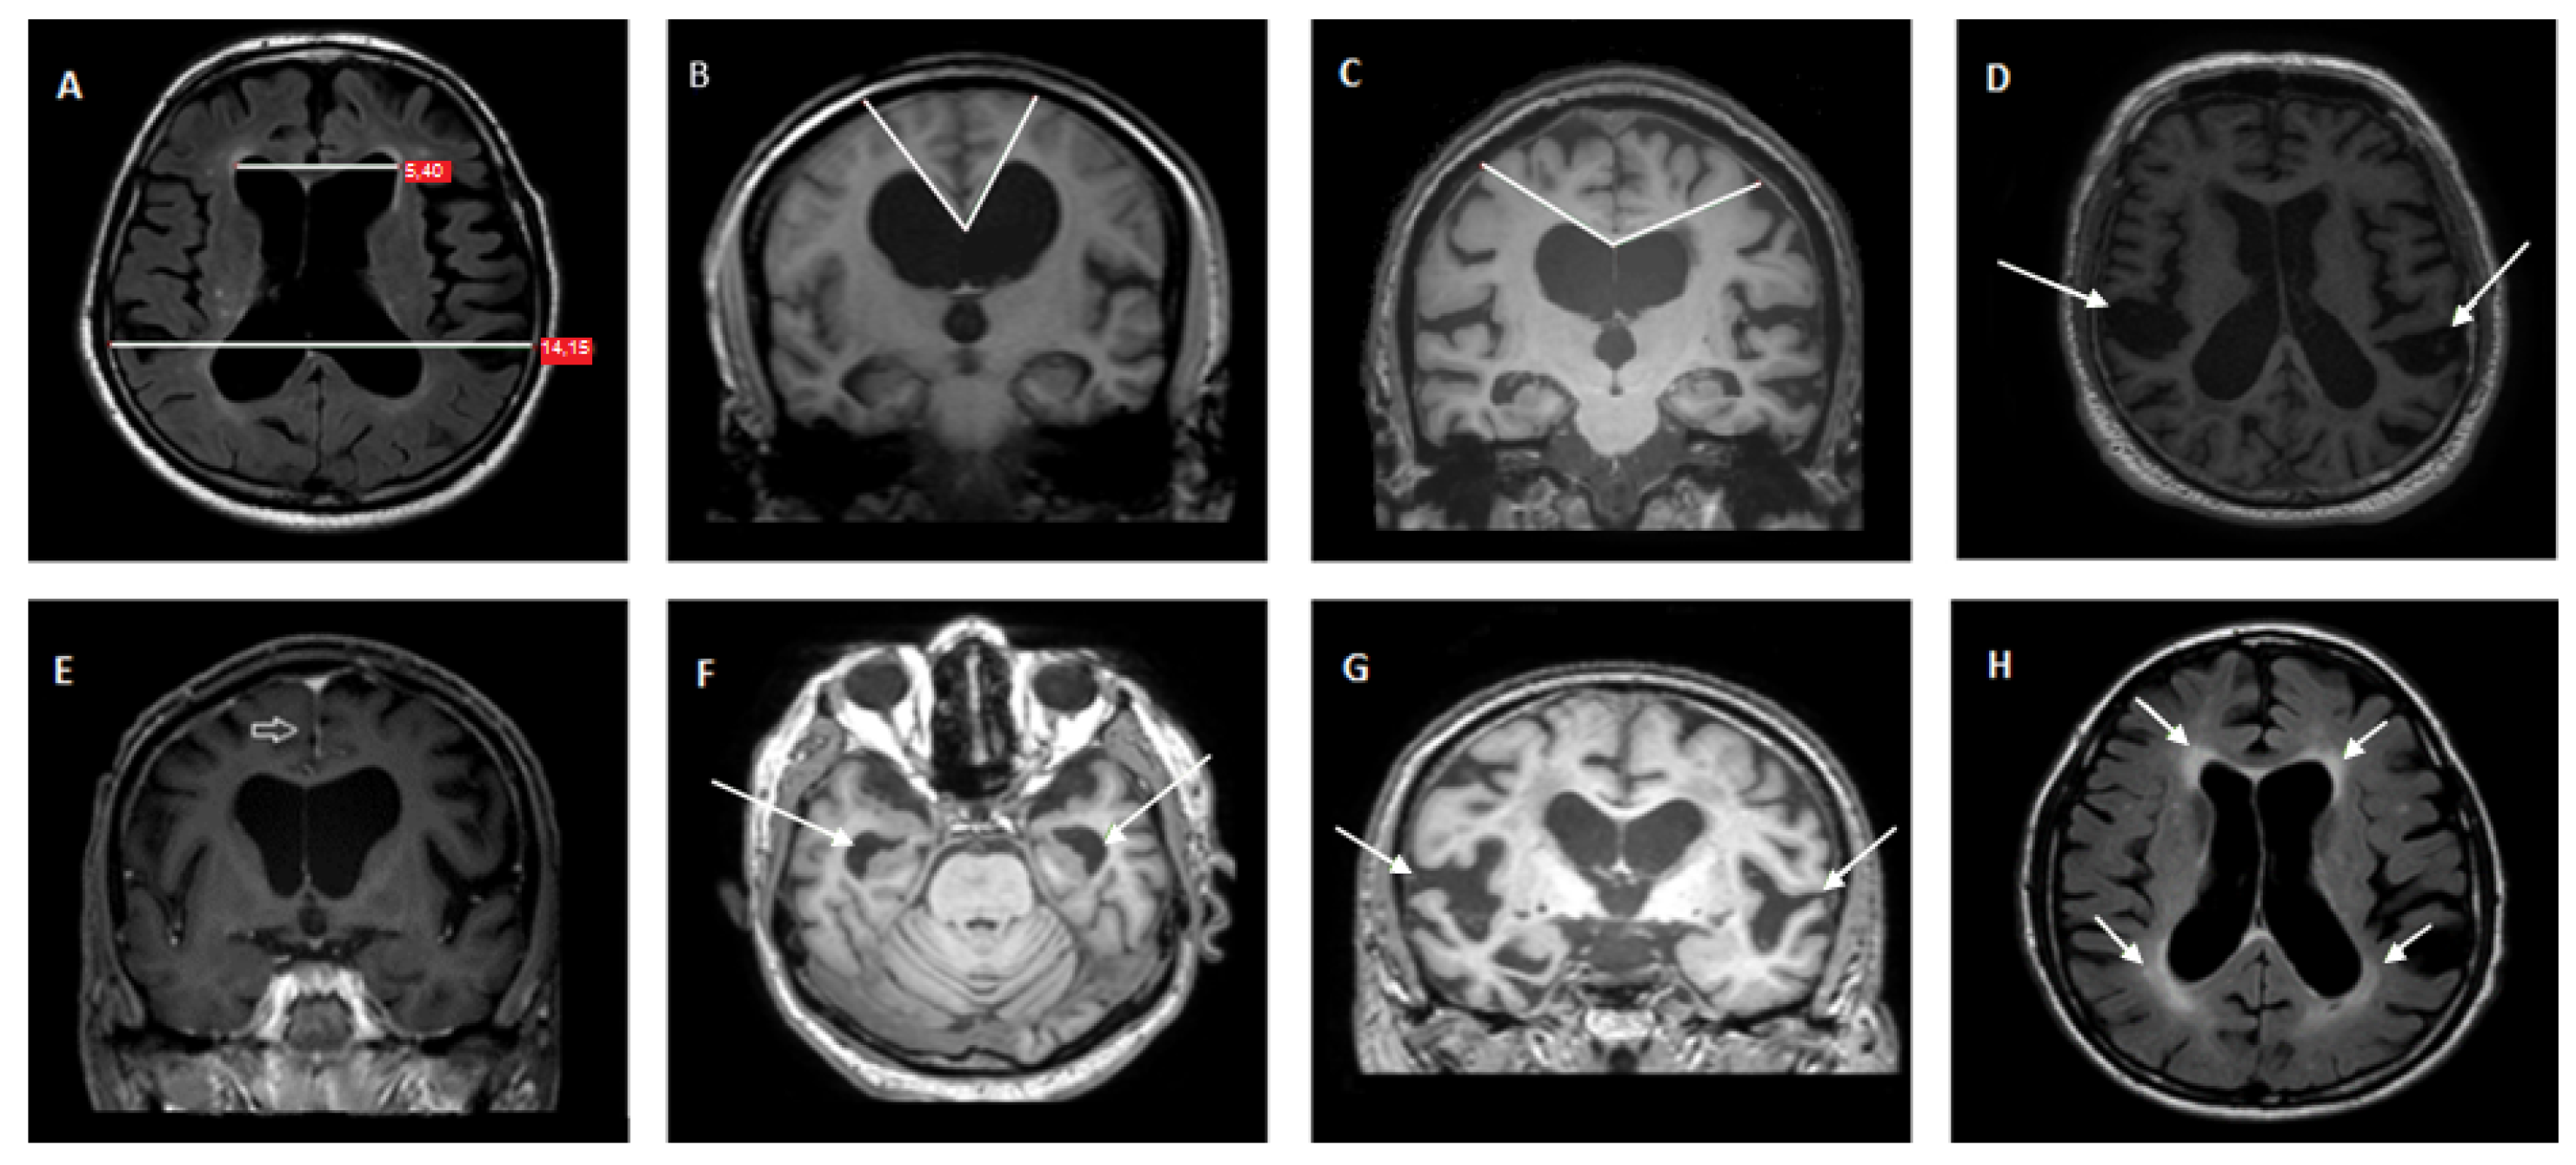

2.3. Magnetic Resonance Imaging

- Kockum, K.; Lilja-Lund, O.; Larsson, E.M.; Rosell, M.; Soderstrom, L.; Virhammar, J.; Laurell, K. The idiopathic normal-pressure hydrocephalus Radscale: A radiological scale for structured evaluation. Eur. J. Neurol. 2018, 25, 569–576. [Google Scholar] [CrossRef]

- Kockum, K.; Virhammar, J.; Riklund, K.; Soderstrom, L.; Larsson, E.M.; Laurell, K. Standardized image evaluation in patients with idiopathic normal pressure hydrocephalus: Consistency and reproducibility. Neuroradiology 2019, 61, 1397–1406. [Google Scholar] [CrossRef]